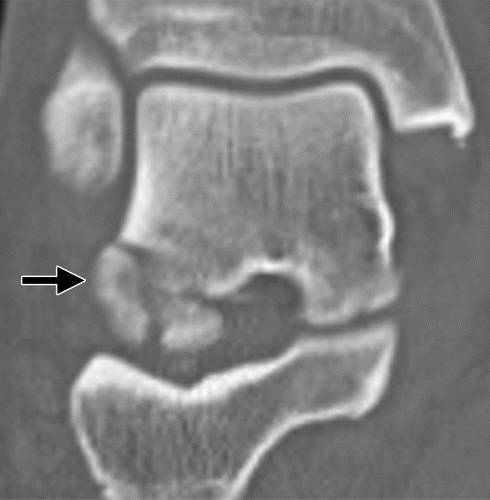

图10a粉碎性骨折冠状剪切距骨体断裂。 (a)该踝的外侧片显示距骨体(箭头)与在后距下关节突骨折碎片的冠剪切断裂。 (b)踝关节的AP射线照片显示后面小面(箭头)的揭示,与后股间关节的半脱位一致。 (c)矢状的CT图像显示了主要在冠状面中的距骨体的粉碎性骨折(箭头)。 在后距下关节处的骨折碎片存在前后牵引,导致半脱位(箭头)。

距骨体的剪切断裂通常由在高度跌倒或机动车辆事故的设置中的背屈脚上的轴向负载引起。 粉碎粉碎的距骨体外骨折对所有距骨损伤的预后最差(24)。 它们通常由于高能量冲击并且经常是开放性骨折。 骨丢失和非解剖复位的发生率高,并且随后出现缺血坏死。

初步诊断可以用放射线摄影,然后进行冠状和矢状重建到踝臼的CT,以评估粉碎,关节内累及手术计划(1,25,26)。